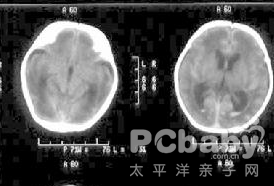

3.長期癲癇發作可能是低鈣血症引起,其中症狀性癲癇在低鈣糾正後完全緩解,如果癲癇仍有發作,考慮與長期低鈣引起的腦內鈣化有關,應進一步尋找原因。